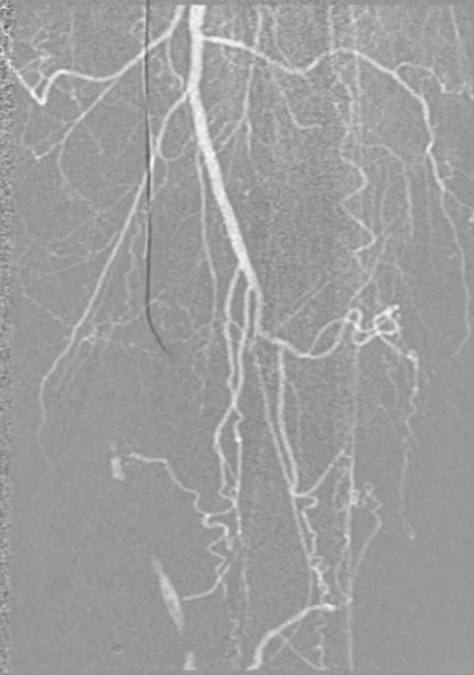

穿刺右侧股总动脉,置入8F翻山鞘,行左下肢动脉造影,可见左股浅动脉长段闭塞,远端流出道尚通畅。

既往支架已遮盖股浅动脉起始段

外院 CTA 提示 “左股浅动脉闭塞(支架内闭塞)”;外周血管超声显示踝肱指数(ABI)左0.42、右0.49,提示左下肢血流灌注明显受损。